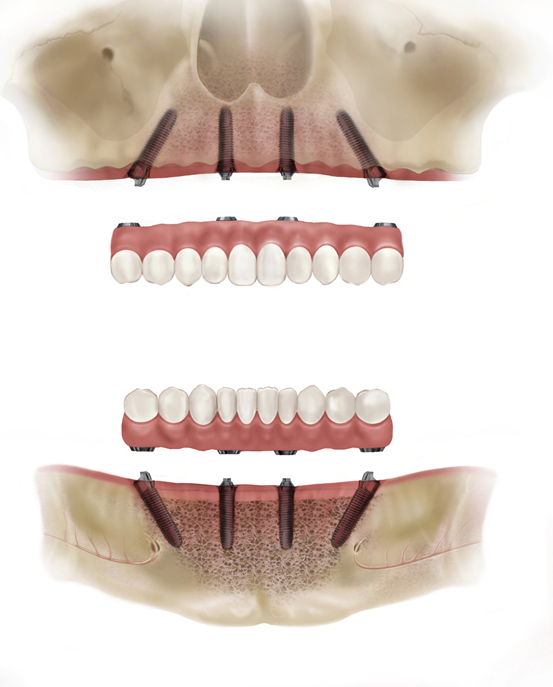

All On Four implant tekniği, tamamen dişsiz çenelere sahip olan hastalara belirli açılarla yerleştirilen dört adet implant dişin üzerine aynı gün geçici olarak hazırlanmış diş protezinin sabitlenmesiyle gerçekleşen bir prosedürdür.

All on four implant tekniğinin geliştirilme amacı alt ve üst çenelerin dişsiz arka bölgelerindeki anatomik kısıtlamalar nedeniyle implant dişin yapılmasının zor yada imkansız olduğu hastalara sabit protez dişin yapılmasına imkan tanımaktır. Bu implant tekniğinde tamamen dişsiz çenelerin ön bölgesine birbirine paralel iki adet implant arka bölgelerine doğru olan kısımlarına ise özel bir açı ile iki adet dental implant yapılır ve aynı gün hastanın kullanabileceği ve implant dişlere sabitlenen bir geçici protez yapılıp ağıza uygulanır.

Daha sonra işlem yapılacak dişsiz çene bölgesi lokal olarak uyuşturulur ve diş eti üzerinde uygun dizaynda kesi yapılarak alttaki kemik doku açığa çıkarılır. Çene kemiği üzerinde gerekli düzenlemeler protez için yapılır ve daha sonraki aşamada cerrahi şablon ile implant diş yapılacak bölgelere uygun yuvalar hazırlanır. Bu alanlara planlanan çap ve boydaki implantlar ön bölgelere birbirine paralel arka bölgelere açılı şekilde yerleştirilir.